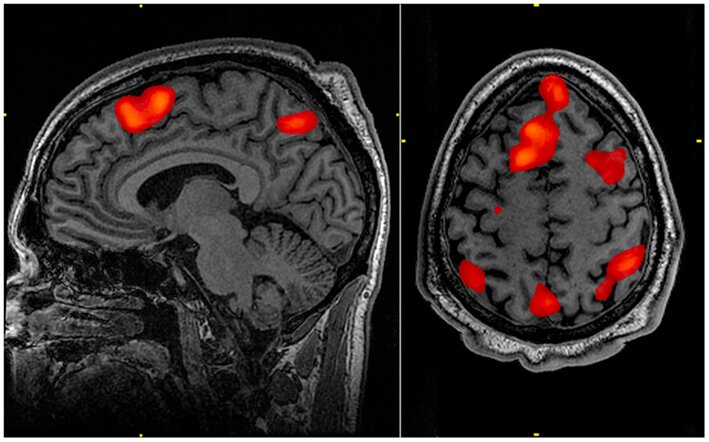

Wraz z rozwojem technologii możliwe jest głębsze poznanie funkcjonowania ludzkiego organizmu. Funkcjonalny rezonans magnetyczny obrazuje wzrost przepływu krwi i utlenowania aktywnej okolicy mózgu. Dzięki badaniom fMRI mózgowia odkryto sieci funkcjonalne odpowiedzialne za uczenie się oraz czytanie.